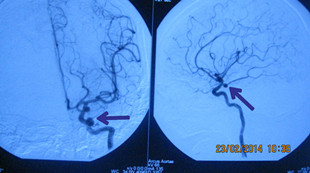

患者韦某某,女性,58岁,因“突发头痛头晕10小时”于2014年2月13日急诊入科,入院CT检查提示:自发性蛛网膜下腔出血。医生给予患者做全脑血管造影(DSA)提示:左侧颈内动脉后交通动脉瘤,大小约(3.0~4.0mm),并行动脉瘤血管内介入栓塞治疗,手术过程顺利,术后患者恢复良好,无神经功能障碍。

血管造影栓塞术后